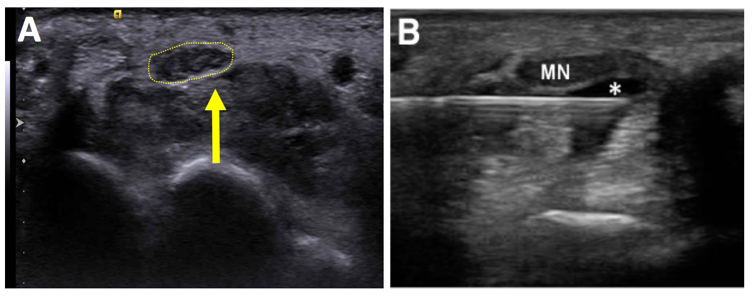

▎一、手肘外側疼痛 ─ 網球肘

長期使用電腦、過度出力或運動後常見之網球肘(肘外側伸肌肌腱病變),臨床上可從位置診斷;但搭配超音波儀器檢測,更可精細診斷肌腱腫脹或發炎,嚴重者可能合併肌腱局部撕裂、橈側副韌帶損傷,或有壓迫周邊細微的皮神經等,此時可考慮搭配局部注射治療。

圖說:超音波影像下,可見手肘外側伸腕肌群的共同肌腱血流增加,意即組織發炎。

圖A箭頭之虛線區:超音波影像顯示患者正中神經腫脹。

圖B:針頭在超音波導引之下進行注射,避免傷及神經或附近肌腱。